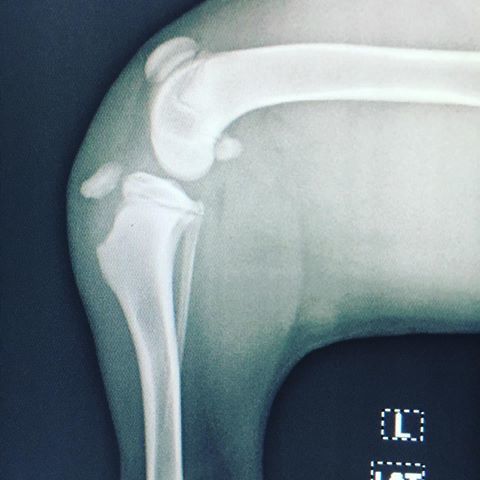

2. Radiografías

1. Resultados

1. Fracturas con desplazamiento